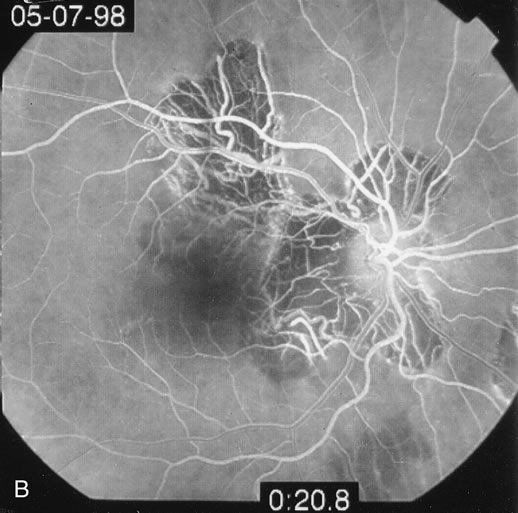

Classically, there are broad areas of chorioretinal atrophy that may take a jigsaw pattern. Usually the atrophy is centered on the disc and spreads along the vascular arcades and then towards the fovea. Sometimes the choroiditis starts within the macula and spreads out from there. Both eyes tend to be affected although there may be marked asymmetry between the two eyes. The active disease appears as yellow-gray areas. If there is evidence of previous disease, then the active areas tend to be at the edge of the chorioretinal atrophy (Figs. 16 to 18). Rarely, there may be several noncontiguous areas of chorioretinal atrophy in the eyes. Retinal vasculitis at the site of an active lesion and retinal vein occlusions may rarely be seen.

Fig. 16. A. Color fundus photograph showing the jigsaw pattern of choroidal and retinal atrophy extending from the disc along the arcades. At the inferior edge of the superotemporal lesion there is a recurrence noted by the grayness of the retina. B. Fluorescein angiogram in the laminar venous phase showing a large window defect in the area of inactive choroiditis and blockage of the choroidal fluorescence in the area of active choroiditis. C. In the late phase of the fluorescein angiogram there is staining of the edges of the inactive choroiditis and marked hyperfluorescence in the area of active choroiditis.

Fig. 17. A. Classic inactive case of serpiginous choroiditis showing the jigsaw pattern of disease surrounding the fovea. B. Fluorescein angiogram showing staining of the edges of the inactive serpiginous choroiditis. There is blocked fluorescence in the areas of hyperplasia of the retinal pigment epithelium. C. Indocyanine green angiogram showing absence of fluorescence in the area of inactive choroiditis.

Fig. 18. Fundus photograph of active macular serpiginous. Because there is no previous evidence of scarring, it is difficult to distinguish by ophthalmoscopy alone from acute posterior multifocal placoid pigment epitheliopathy (APMPPE). The larger size and the age of the patient tend to help in distinguishing.